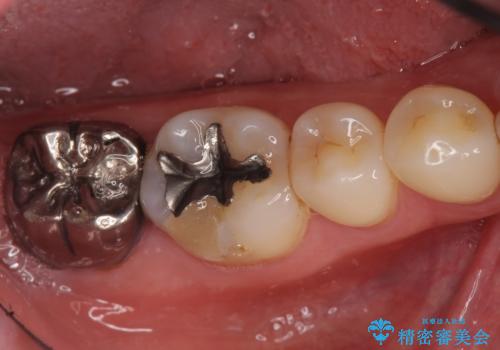

歯ぐきの深い位置まで虫歯が 歯周外科→被せもの による奥歯の治療

多発した縁下カリエス 歯周外科を併用する虫歯治療